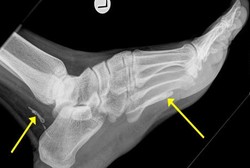

Tak Cuma di Paru, Kuman TB Juga Bisa 'Bersarang' di Tulang

Tuberculosis alias TB nyatanya tidak hanya terjadi di sistem pernapasan saja seperti pada umumnya. Sebab, TB pun bisa dialami bagian tubuh lain yakni tulang.